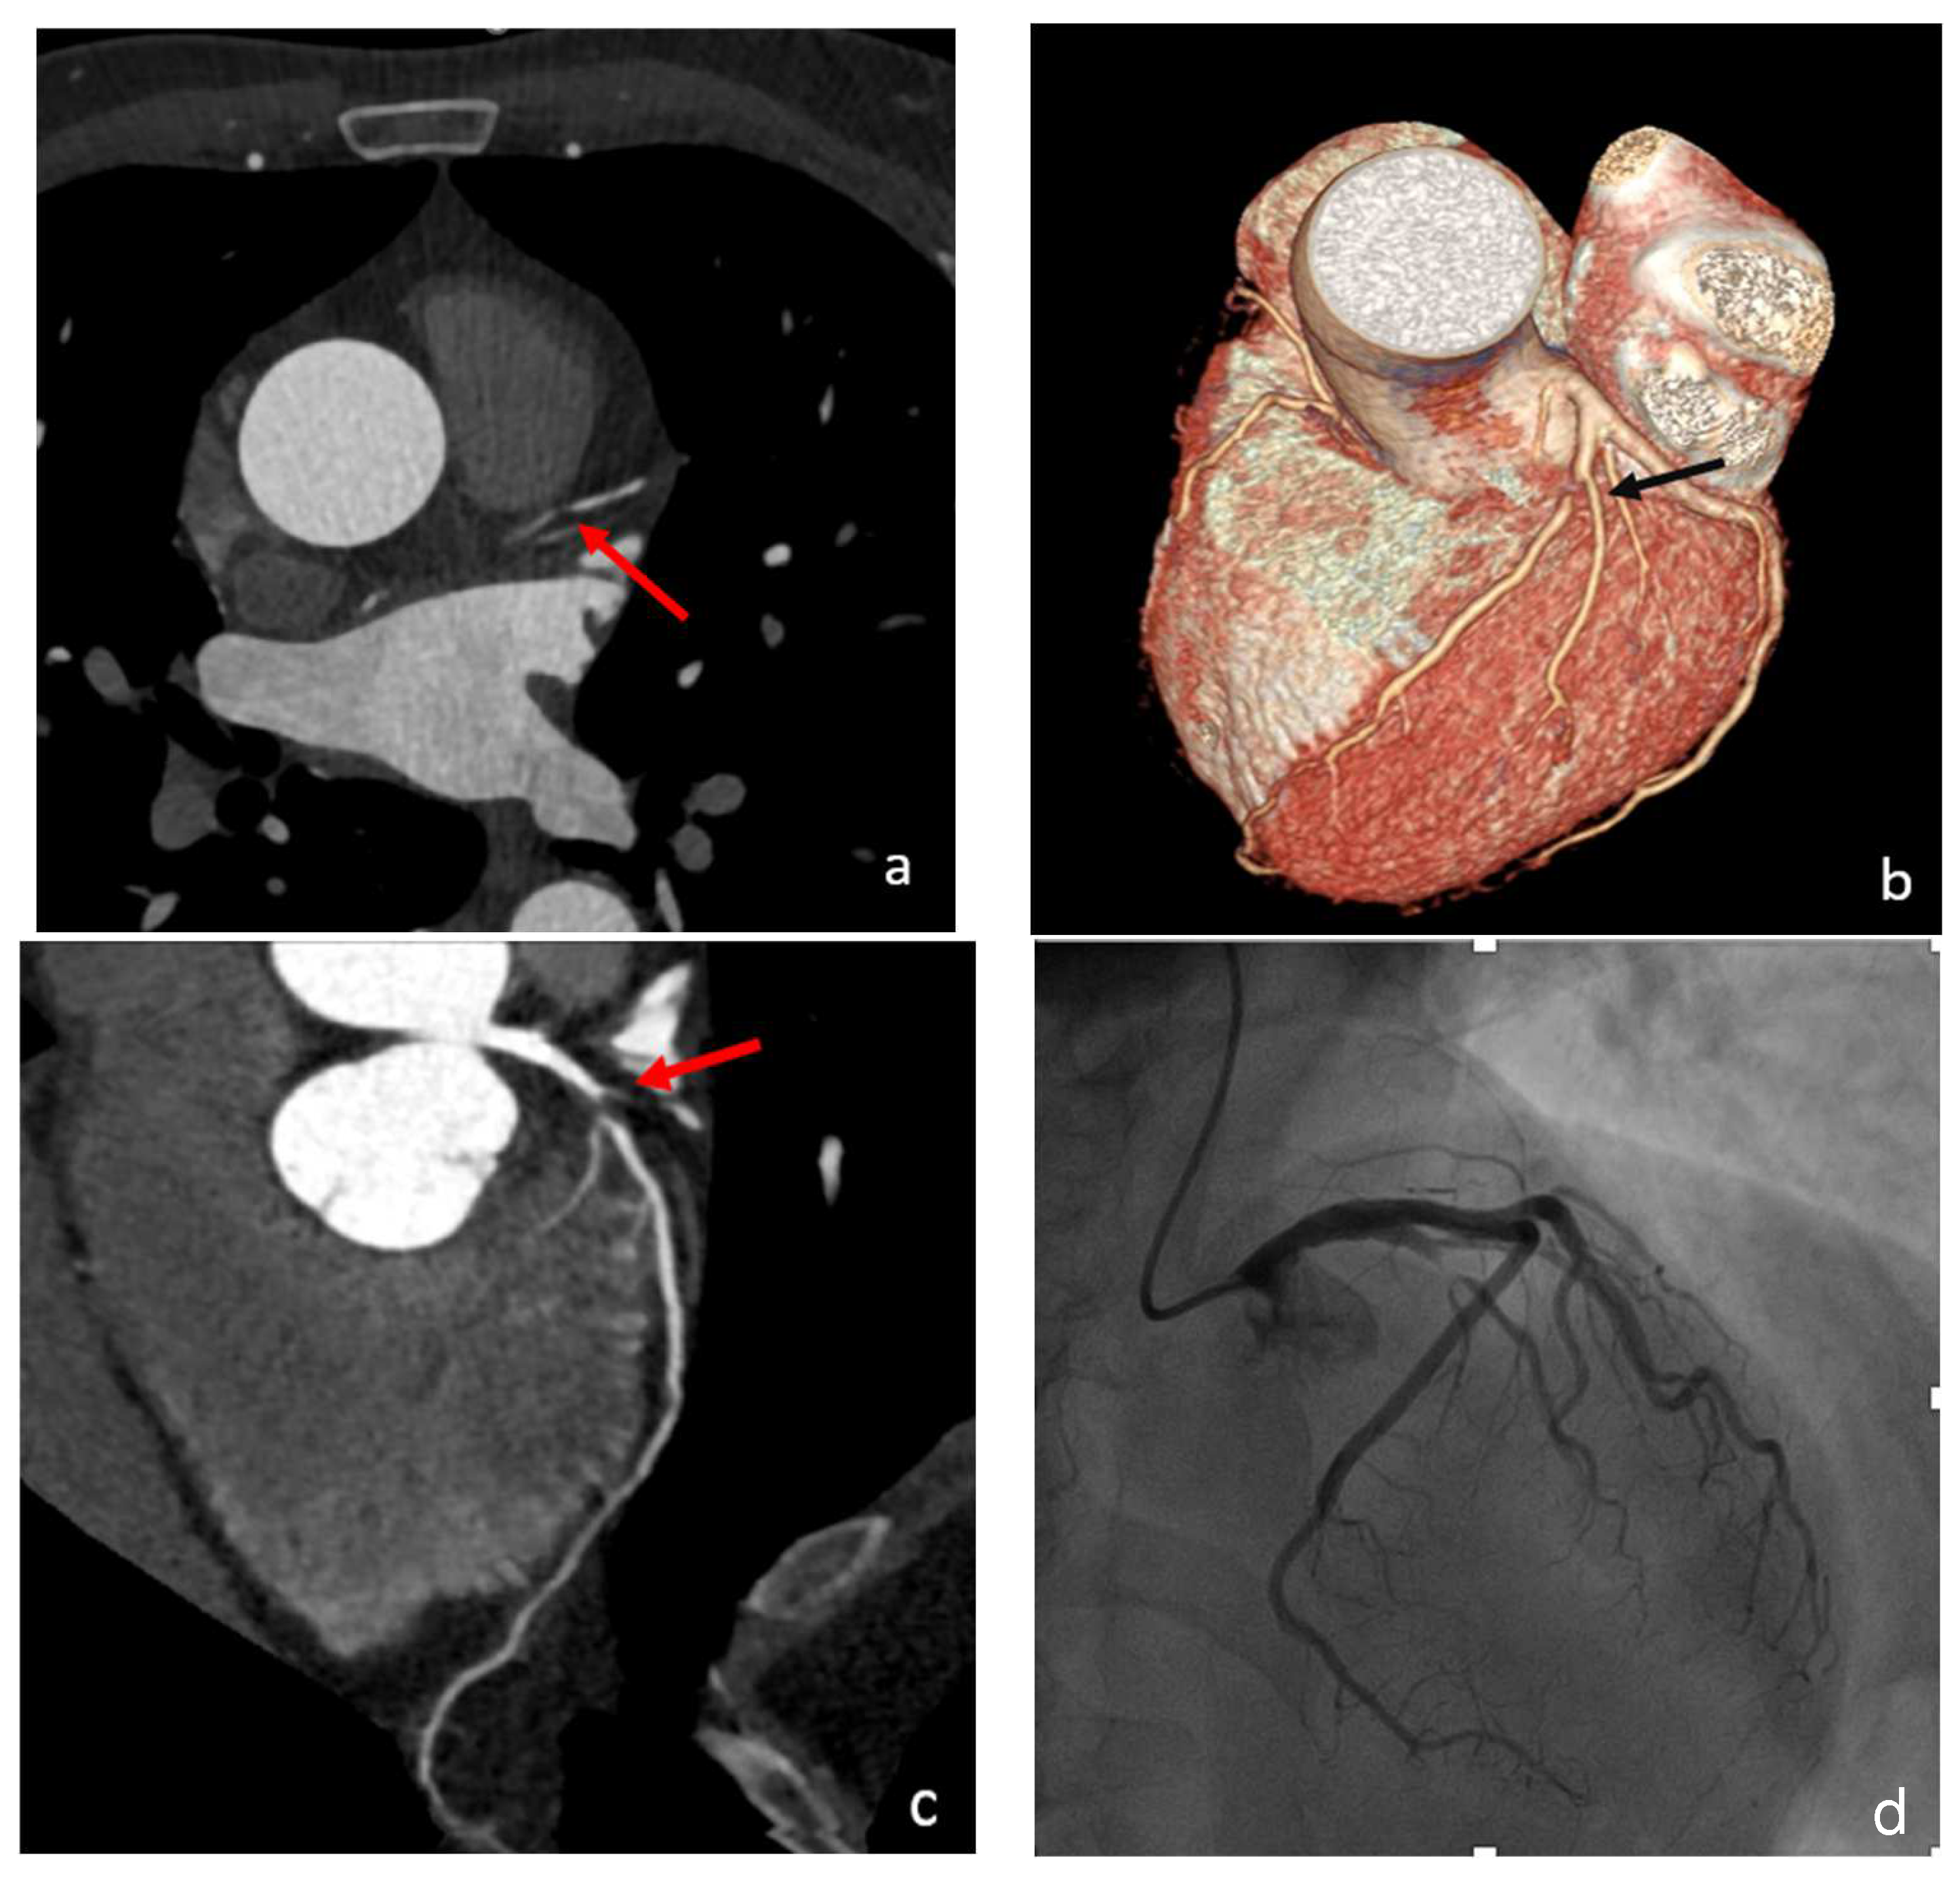

- Gupta, S.; Meyersohn, N.M.; Wood, M.J.; Steigner, M.L.; Blankstein, R.; Ghoshhajra, B.B.; Hedgire, S.S. Role of Coronary CT Angiography in Spontaneous Coronary Artery Dissection. Radiol. Cardiothorac. Imaging 2020, 2, e200364. [Google Scholar] [CrossRef]

- Aslam, A.; Stojanovska, J.; Khokhar, U.S.; Weinberg, R.L.; Ganesh, S.K.; Labounty, T.; Sutton, N.R.; Patel, S. Spontaneous Coronary Artery Dissection: An Underdiagnosed Clinical Entity-A Primer for Cardiac Imagers. RadioGraphics 2021, 41, 1897–1915. [Google Scholar] [CrossRef]

- Marrazzo, G.; Palermi, S.; Pastore, F.; Ragni, M.; De Luca, M.; Gambardella, M.; Quaranta, G.; Messalli, G.; Riegler, L.; Pergola, V.; et al. Multimodality Imaging Approach to Spontaneous Coronary Artery Dissection. J. Clin. Med. 2022, 12, 154. [Google Scholar] [CrossRef]

- Sun, Y.; Mao, D.; Lu, F.; Chen, Y.; Shi, K.; Qi, L.; Guo, X.; Hua, Y. Diagnosis of Dissection of the Coronary Artery Dissection by Multidetector Computed Tomography: A Comparative Study with Coronary Angiology. J. Comput. Assist. Tomogr. 2015, 39, 572–577. [Google Scholar] [CrossRef]

- Roura, G.; Ariza-Solé, A.; Rodriguez-Caballero, I.F.; Gomez-Lara, J.; Ferreiro, J.L.; Romaguera, R.; Teruel, L.; de Albert, M.; Gomez-Hospital, J.A.; Cequier, A. Noninvasive Follow-Up of Patients with Spontaneous Coronary Artery Dissection with CT Angiography. JACC Cardiovasc. Imaging 2016, 9, 896–897. [Google Scholar] [CrossRef]

- Tweet, M.S.; Akhtar, N.J.; Hayes, S.N.; Best, P.J.; Gulati, R.; Araoz, P.A. Spontaneous Coronary Artery Dissection: Acute Findings on Coronary Computed Tomography Angiography. Eur. Heart J. Acute Cardiovasc. Care 2019, 8, 467–475. [Google Scholar] [CrossRef]

- Bin Saeedan, M.; Ramchand, J.; Bolen, M. Role of Computed Tomography Angiography in Setting of Spontaneous Coronary Artery Dissection. Curr. Probl. Diagn. Radiol. 2021, 50, 532–539. [Google Scholar] [CrossRef]